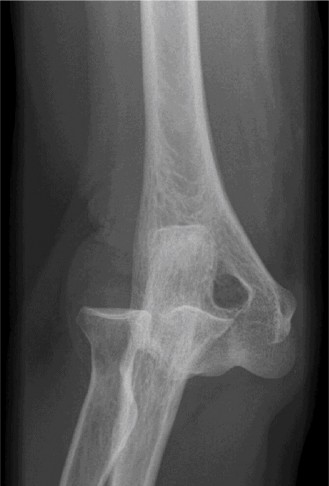

Examination reveals deformity about the elbow with no open lesions or skin tenting. He has a palpable radial and ulnar pulse and is neurologically intact. His images are shown (Figs. 2–85 to 2–88).

Figure 2–85

Figure 2–86

Figure 2–87

Figure 2–88

What is the diagnosis and direction of displacement?

- Monteggia fracture dislocation, posterolateral displacement of the forearm about the humerus

- Simple elbow dislocation, posterolateral displacement of the forearm about the humerus

- Transolecranon complex elbow dislocation

- Simple elbow dislocation, posteromedial displacement of the forearm about the humerus

Discussion

The correct answer is (B). This is the most common type of elbow dislocation, and often does not cause any osseous injury. Posterolateral and posteromedial dislocation account for approximately 90% of dislocations. Adequate pre- and postreduction films are necessary to evaluate for fracture, which would change the classification to a complex injury.